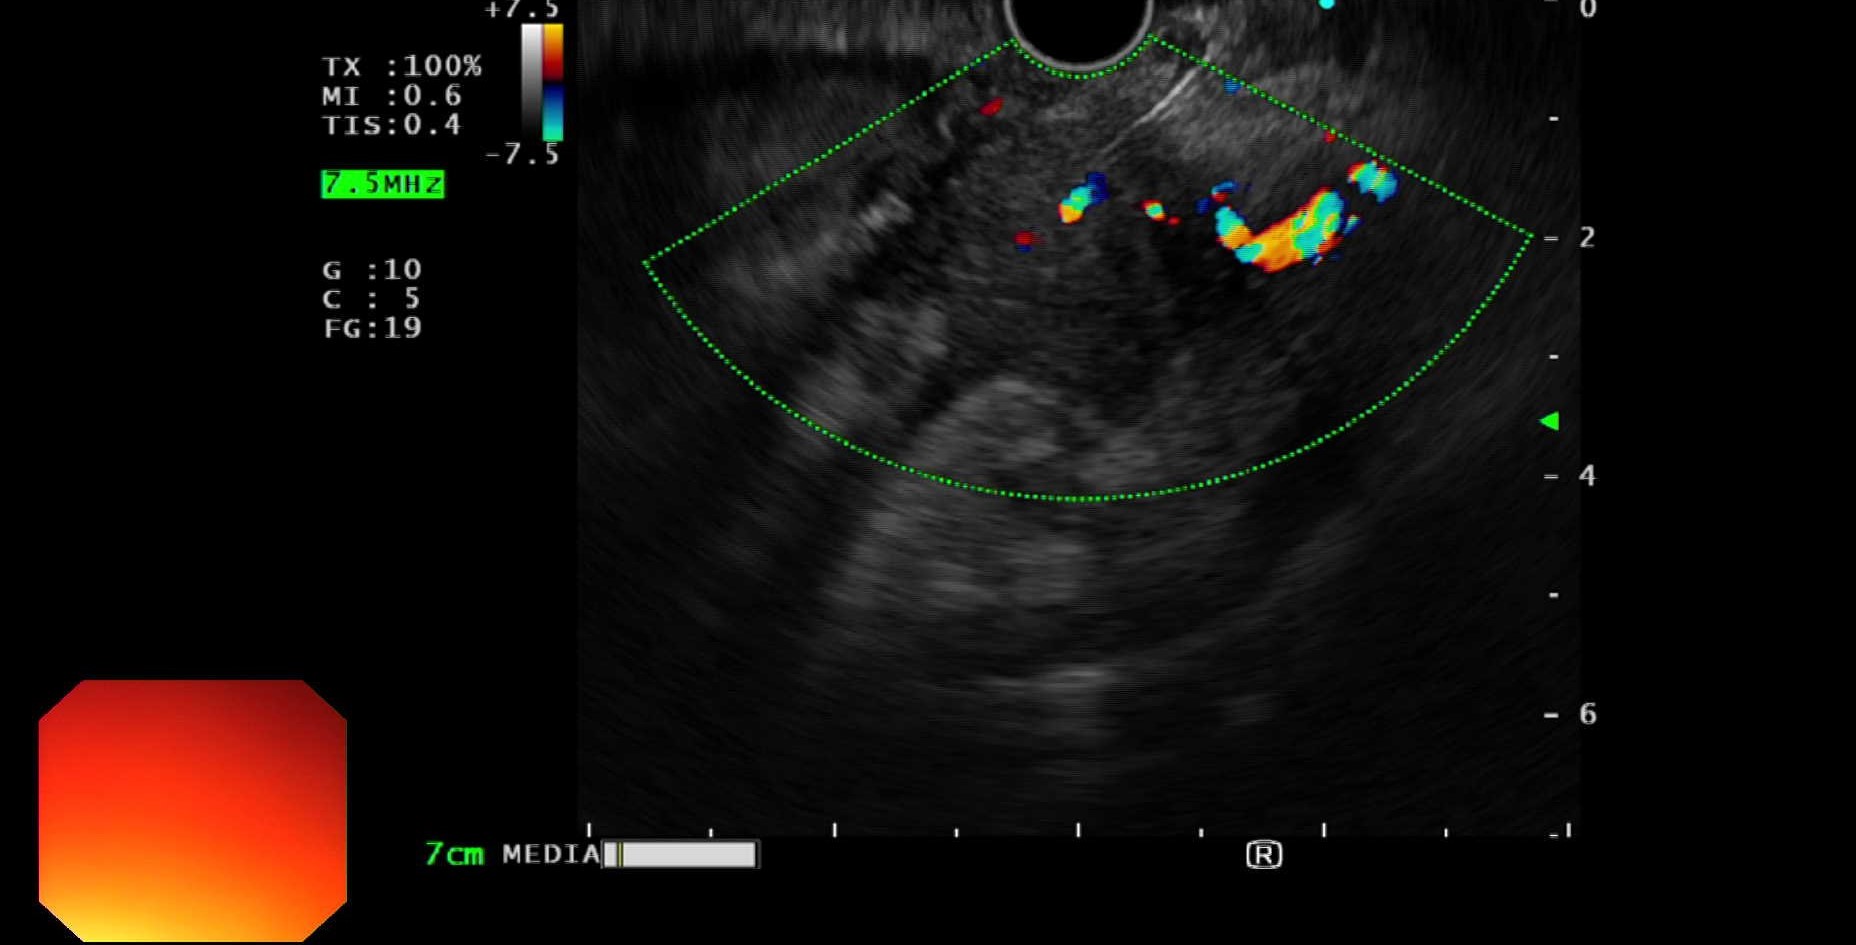

Chọc hút tế bào bằng kim nhỏ dưới hướng dẫn của nội soi siêu âm (EUS-FNA) là một thủ thuật xâm lấn tối thiểu, được tiến hành tương tự như nội soi dạ dày có gây mê. Do đầu dò siêu âm được gắn ở đầu dây soi sẽ áp sát vào các khối u tụy qua đường dạ dày – tá tràng nên nội soi siêu âm giúp định vị đúng, đánh giá một cách toàn diện về kích thước, ranh giới, mức độ xâm lấn của tổn thương và giúp tránh được các mạch máu lớn. Đồng thời, dưới hướng dẫn của nội soi siêu âm, một cây kim chọc hút nhỏ (FNA) sẽ được đưa qua kênh sinh thiết của dây soi vào trong khối u để lấy bệnh phẩm chính xác nhất, hạn chế tối đa việc lấy nhầm ở vị trí lành hay hoại tử. Từ đó cho chẩn đoán chính xác về tính chất của khối u và là căn cứ để các bác sĩ lâm sàng xây dựng phác đồ điều trị tốt nhất cho người bệnh.

Khoa Tiêu hóa – Nội soi, Bệnh viện đa khoa Quốc tế Hải Phòng đã triển khai hiệu quả kỹ thuật trên, mang lại cơ hội điều trị sớm cho người bệnh. Điển hình là 2 trường hợp bệnh nhân V.X.Đ, 55 tuổi, ở Hưng Hà, Thái Bình và bệnh nhân B.Đ.V, 63 tuổi ở Cát Dài, Lê Chân, đi khám phát hiện thấy khối u vùng thân tụy. Cả 2 bệnh nhân đều được chỉ định làm nội soi siêu âm can thiệp chọc hút tế bào khối u tụy bằng kim nhỏ để làm giải phẫu bệnh. Kết quả đều là: Ung thư biểu mô tuyến xâm nhập. Như vậy, việc phát hiện sớm và xác định chính xác tính chất khối u là ác tính đã góp phần làm tăng cơ hội điều trị với tỷ lệ hồi phục cao cho người bệnh.